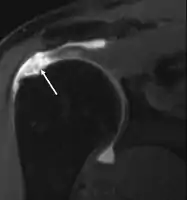

MRI

MRI of normal shoulder intratendinous signal

MRI of rotator cuff full-thickness tear

Magnetic resonance imaging (MRI) and ultrasound[42] are comparable in efficacy and helpful in diagnosis although both have a false positive rate of 15 - 20%.[43] MRI can reliably detect most full-thickness tears although very small pinpoint tears may be missed. In such situations, an MRI combined with an injection of contrast material, an MR-arthrogram, may help to confirm the diagnosis. It should be realized that a normal MRI cannot fully rule out a small tear (a false negative) while partial-thickness tears are not as reliably detected.[44] While MRI is sensitive in identifying tendon degeneration (tendinopathy), it may not reliably distinguish between a degenerative tendon and a partially torn tendon. Again, magnetic resonance arthrography can improve the differentiation.[44] An overall sensitivity of 91% (9% false negative rate) has been reported indicating that magnetic resonance arthrography is reliable in the detection of partial-thickness rotator cuff tears.[44] However, its routine use is not advised, since it involves entering the joint with a needle with potential risk of infection. Consequently, the test is reserved for cases in which the diagnosis remains unclear.